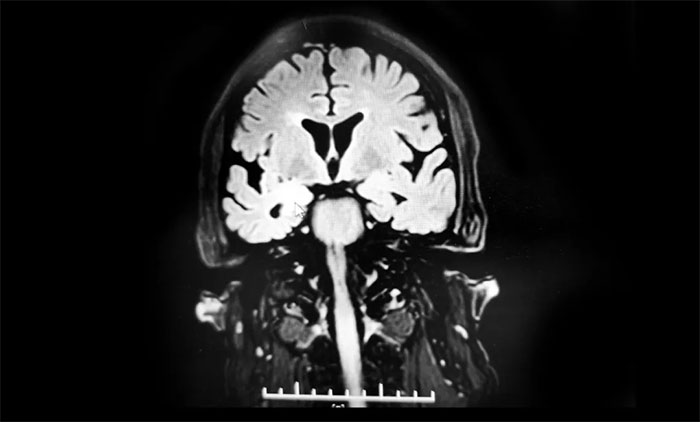

結(jié)合患者癥狀、病史,張靜波主任考慮并不是單純癲癇發(fā)作那么簡單。頭顱核磁平掃、增強沒有發(fā)現(xiàn)問題,但是海馬核磁檢查發(fā)現(xiàn)異常:雙側(cè)海馬萎縮,右側(cè)為著伴右側(cè)海馬信號增高,需要考慮炎癥、免疫、腫瘤等多種可能。

▲ 海馬核磁檢查發(fā)現(xiàn)異常:雙側(cè)海馬萎縮,右側(cè)為著伴右側(cè)海馬信號增高